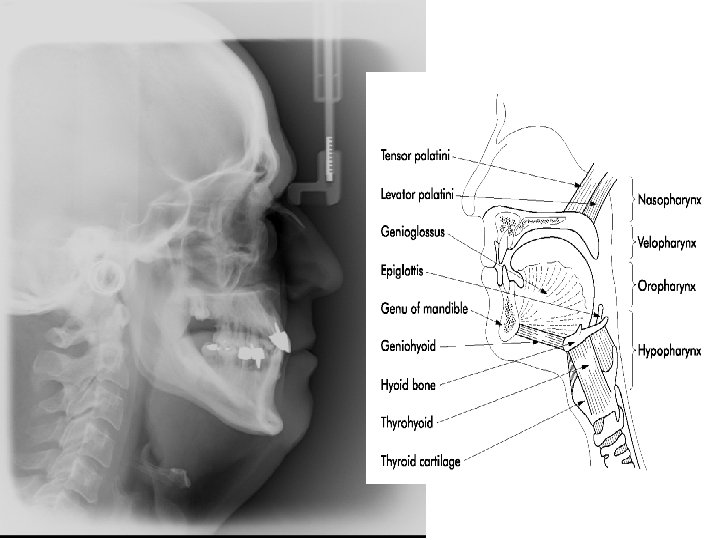

Meccanismo d’azione della CPAP Pressione a monte 0. 0 cm/H 2 O 5 cm/H

Meccanismo d’azione della CPAP Pressione a monte 0. 0 cm/H 2 O 5 cm/H 2 O Starling resistor 10 cm/H 2 O 15 cm/H 2 O Pressione a valle

Courtesy of Giuseppe Insalaco